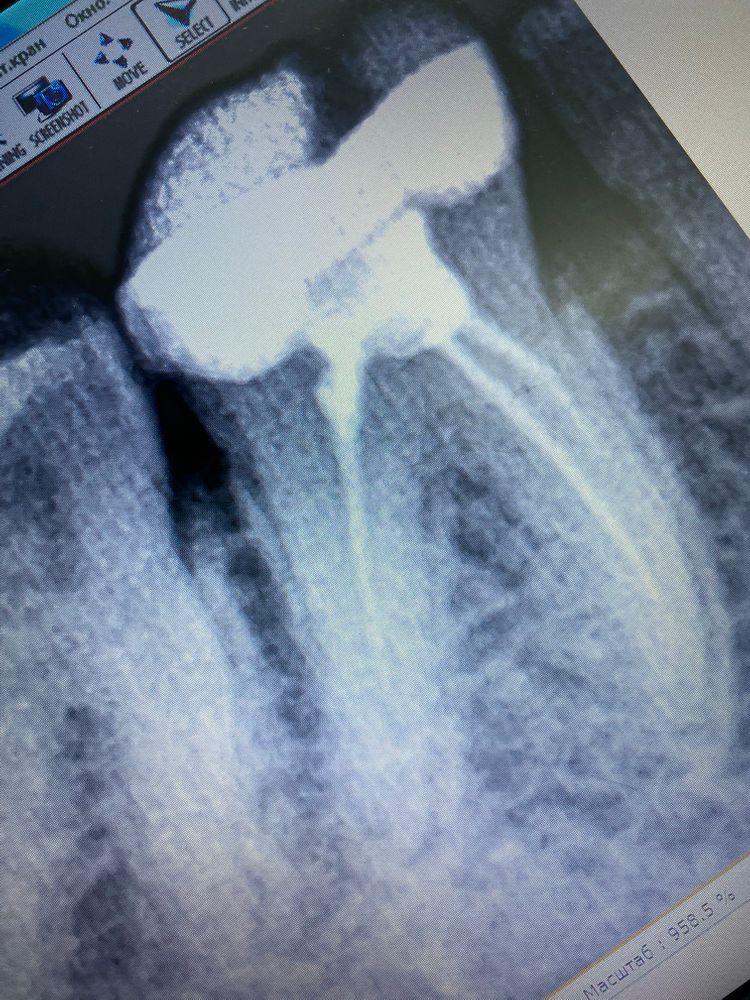

Kristina 4 года Сделали зуб не болит, но сделала снимок не видно , должна ли быть пломба до конца корня, или все пра Посмотрите еще 20 записей на эту тему Отменить Ответить Kristina 14.02.2022 Ответить Мария Мария Kristina, а стоматолог что сказала? 14.02.2022 Ответить У сына аллергия после года жуткая вылезла Ребёнок прыгает на одном месте Чаты Беременных Выберите чат: Январята-2026 Февралята-2026 Мартята-2026 Апрелята-2026 Майчата-2026 Июнята-2026 Июлята-2026 Августята-2026